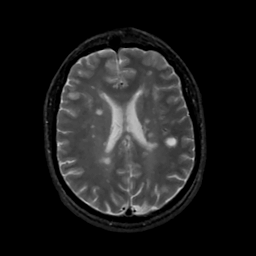

MR Study #15, June 9, 1991 -- Slice #31